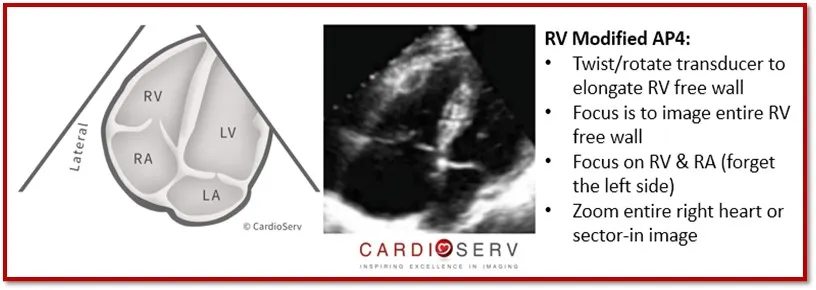

RV modified AP4 view

RV free wall이 위로 올라오게

약간은 foreshotening됨.

TV에 수직이 되어 doppler 측정에 용이해짐

RV linear dimesions (ouflow)